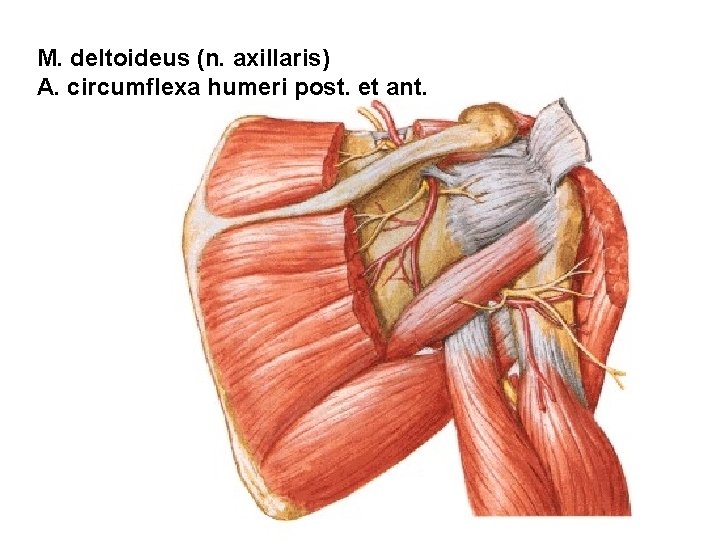

M. deltoideus (n. axillaris) A. circumflexa humeri post. et ant.